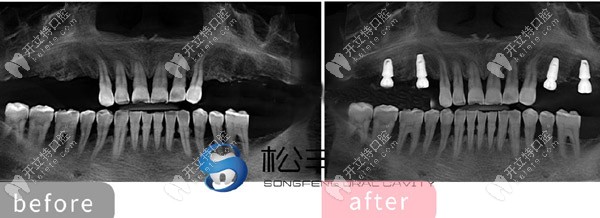

★ 顧客下頜多顆缺失,

上海松豐齒科的蔣院長采用了即刻種植技術(shù),讓顧客當天就了下半口牙。

下頜即刻種植

★ 多顆牙齒缺失種植展示

多顆牙齒缺失種植展示